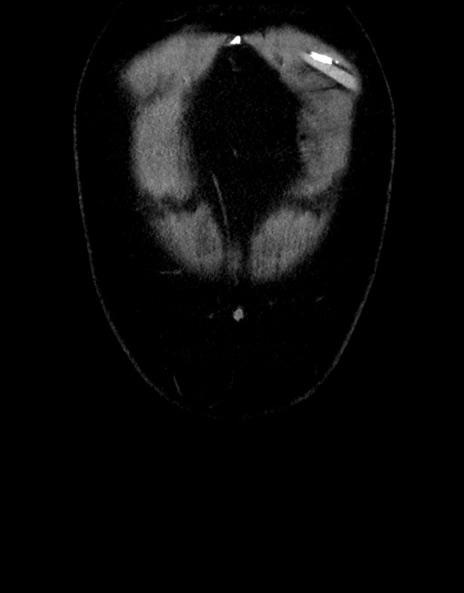

横断像

【症例】70歳代男性

【主訴】腹痛

【現病歴】今朝から腹痛あり。全体的に痛い。特に左上の方。排ガスが今日はない。冷や汗が出る。

【既往歴】直腸癌術後

【身体所見】左側腹部〜上腹部に圧痛あり。腹膜刺激症状明らかなではない。軽度反跳痛。左下腹部に術後瘢痕あり。

【データ】WBC 7700、CRP 0.02